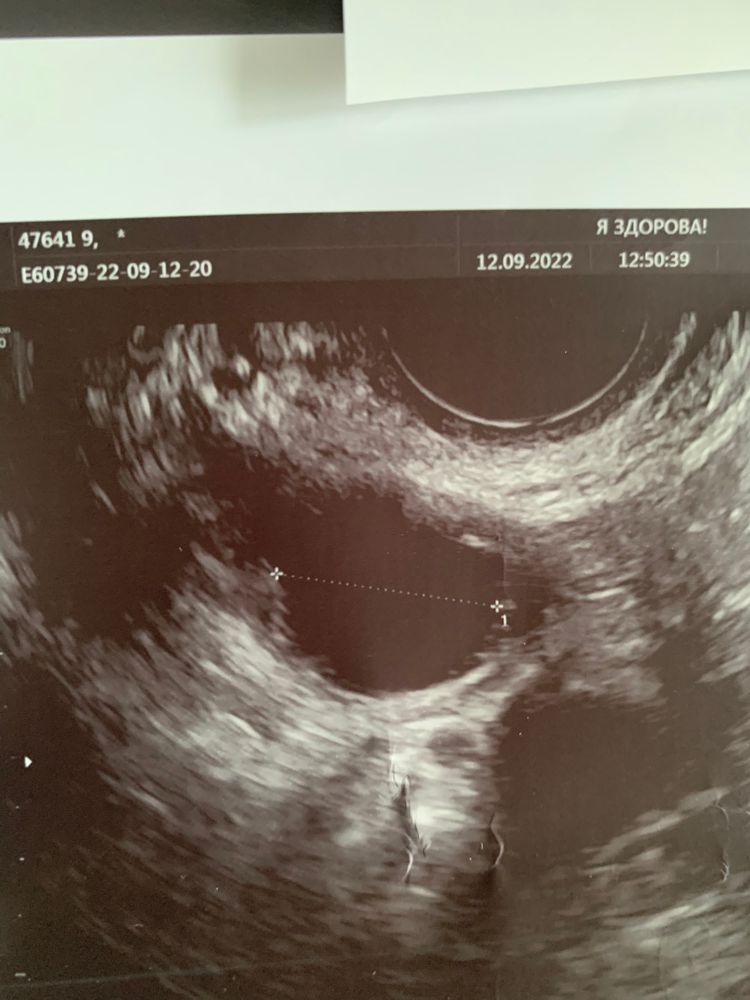

Natali, вот с такой картинкой нп такой же день цикла в сентябре мне другой специалист ставил ДФ) но тут менее сплющенное.

но вот в сентябре на узи похожая форма на тот же день цикла и примерно такие ж размеры, ставили ДФ